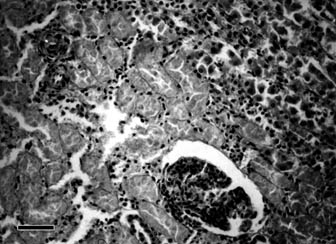

Histological examination of kidneys revealed granular or hyaline droplet degeneration, desquamation, as well small necroses. These were more pronounced in the epithelium of proximal convoluted tubules in cortex (Fig. 1) compared to the distal ones. In some regions of the cortex and medulla small haemorrhages and mononuclear cell infiltration were observed. Some of the glomerules were hypercellular, exhibiting slight endothelial or mesangial proliferation. The capillaries in the medulla were hyperaemic. Degenerative changes in proximal tubules were predominant in early stages (on the 10th day), whereas in later stages (on the 30th day) there was also slight proliferation of connective tissue and mononuclear cell infiltration in the interstitium, as well thickened basement tubular membranes, established by PAS staining. Granular and hyalin casts (proved by ironhematoxylin-Van Gieson staining) or proteinaceous debris in the lumen were observed in some convoluted or collected tubules (Fig. 2).

Fig. 1 Photomicrograph of kidney of sheep in group I. Group I was treated

per os with 6×3.5 mg of mercury in 1% mercuric chloride solution, biopsed

using laparotomy on the 10th day of the experiment. Granular degeneration,

karyolysis, desquamation and disintegration of epithelial cells of proximal

tubules.

H/E; 400 ×; bar = 25 µm.